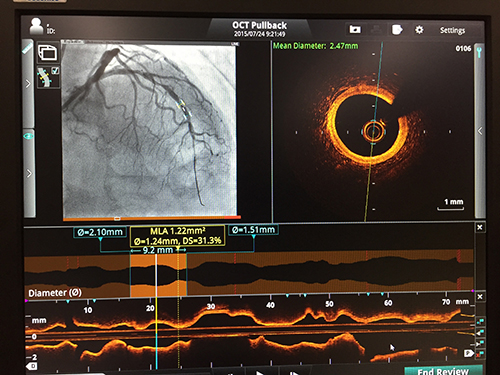

心臓血管カテーテル検査及び治療業務においては、外回り業務としてポリグラフの操作、血管内イメージングデバイス(Intra Vascular Ultra Sound: IVUSやOptical Coherence Tomography: OCT)のセットアップ及び操作、検査・治療に必要な物品の管理及び清潔野への物だし、カテーテル治療の経過記録やレポートの作成・管理、IABP (Intra Aortic Balloon Pumping)・PCPS (Percutaneous Cardio Pulmonary Support)などの補助循環装置の操作などを行っています。また、清潔野にて手術台の操作、医師のカテーテル検査及び治療のサポートも行っています。